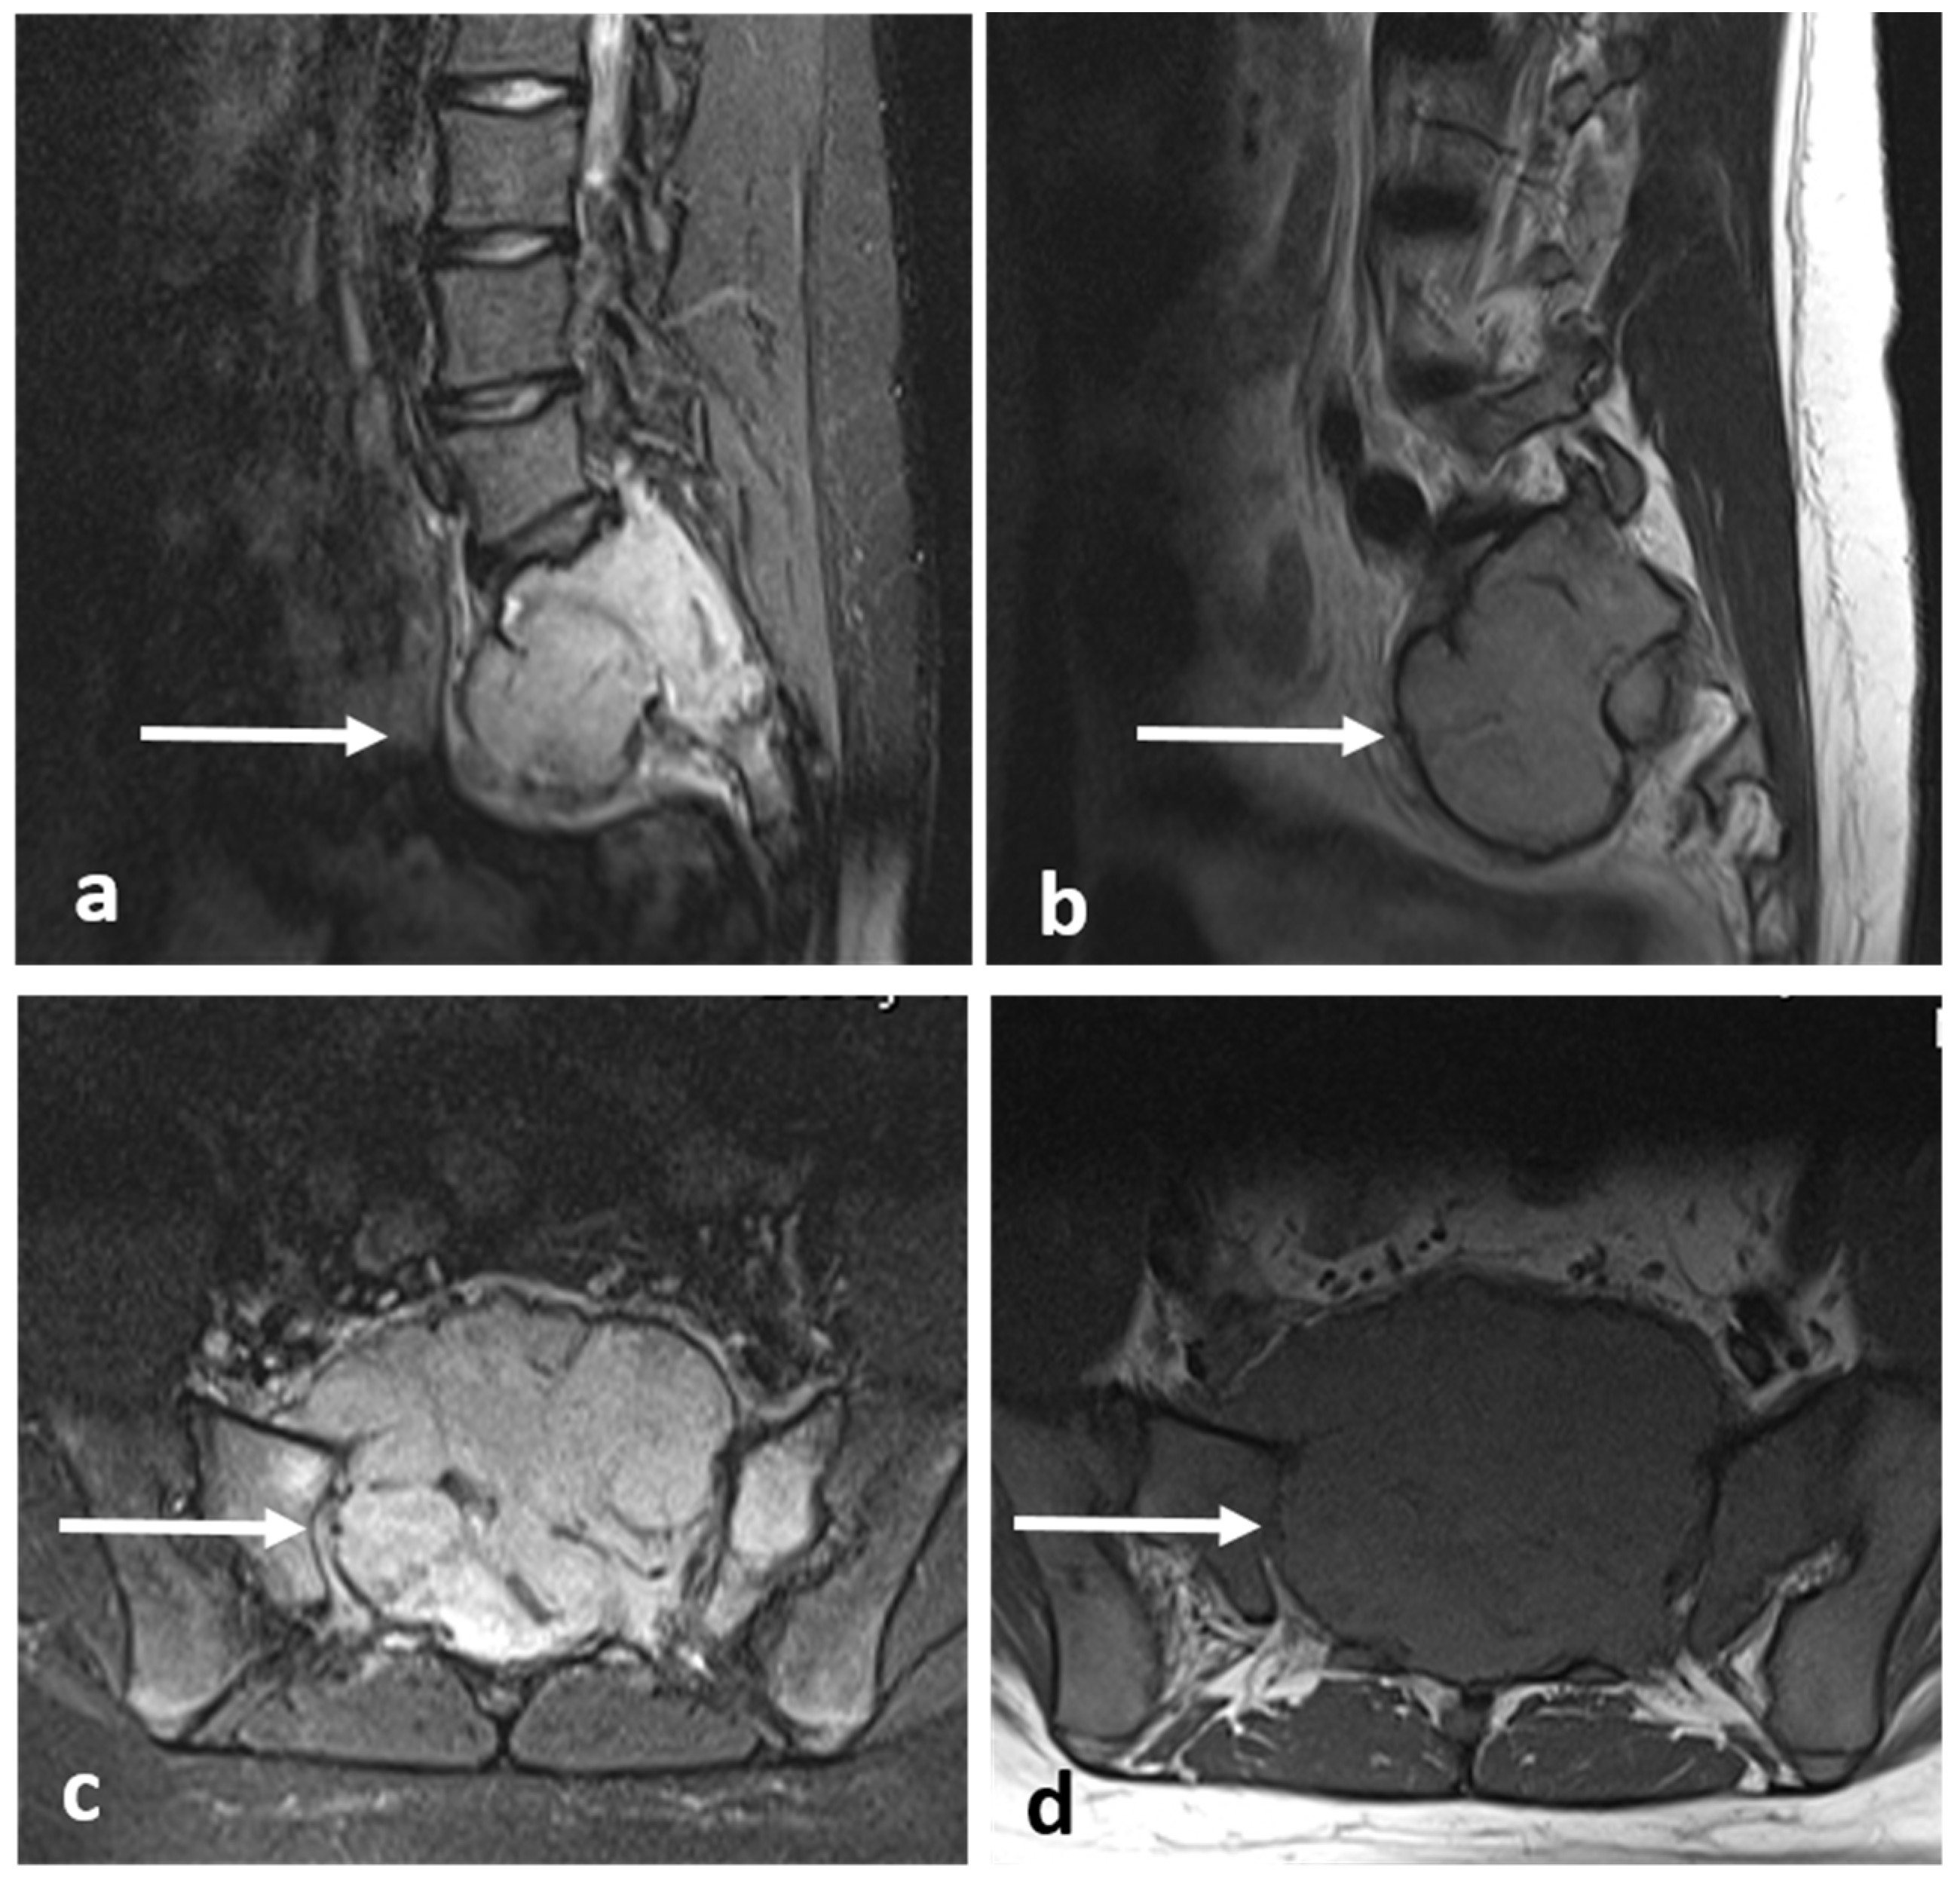

| Aneurysmal bone cyst | Expansile lytic lesion with internal bone septations. | Fluid—fluid levels within the cysts, high T1 signal within layering fluid content due to haemorrhage. |

| Giant cell tumour | Mixed cystic and solid expansile lesions, with thin peripheral bony shell. ‘Soap bubble’ appearance. | Secondary ABC change is common, with fluid—fluid levels. Intermediate to low signal intensity on both T1 and T2. Enhancing soft tissue component. |